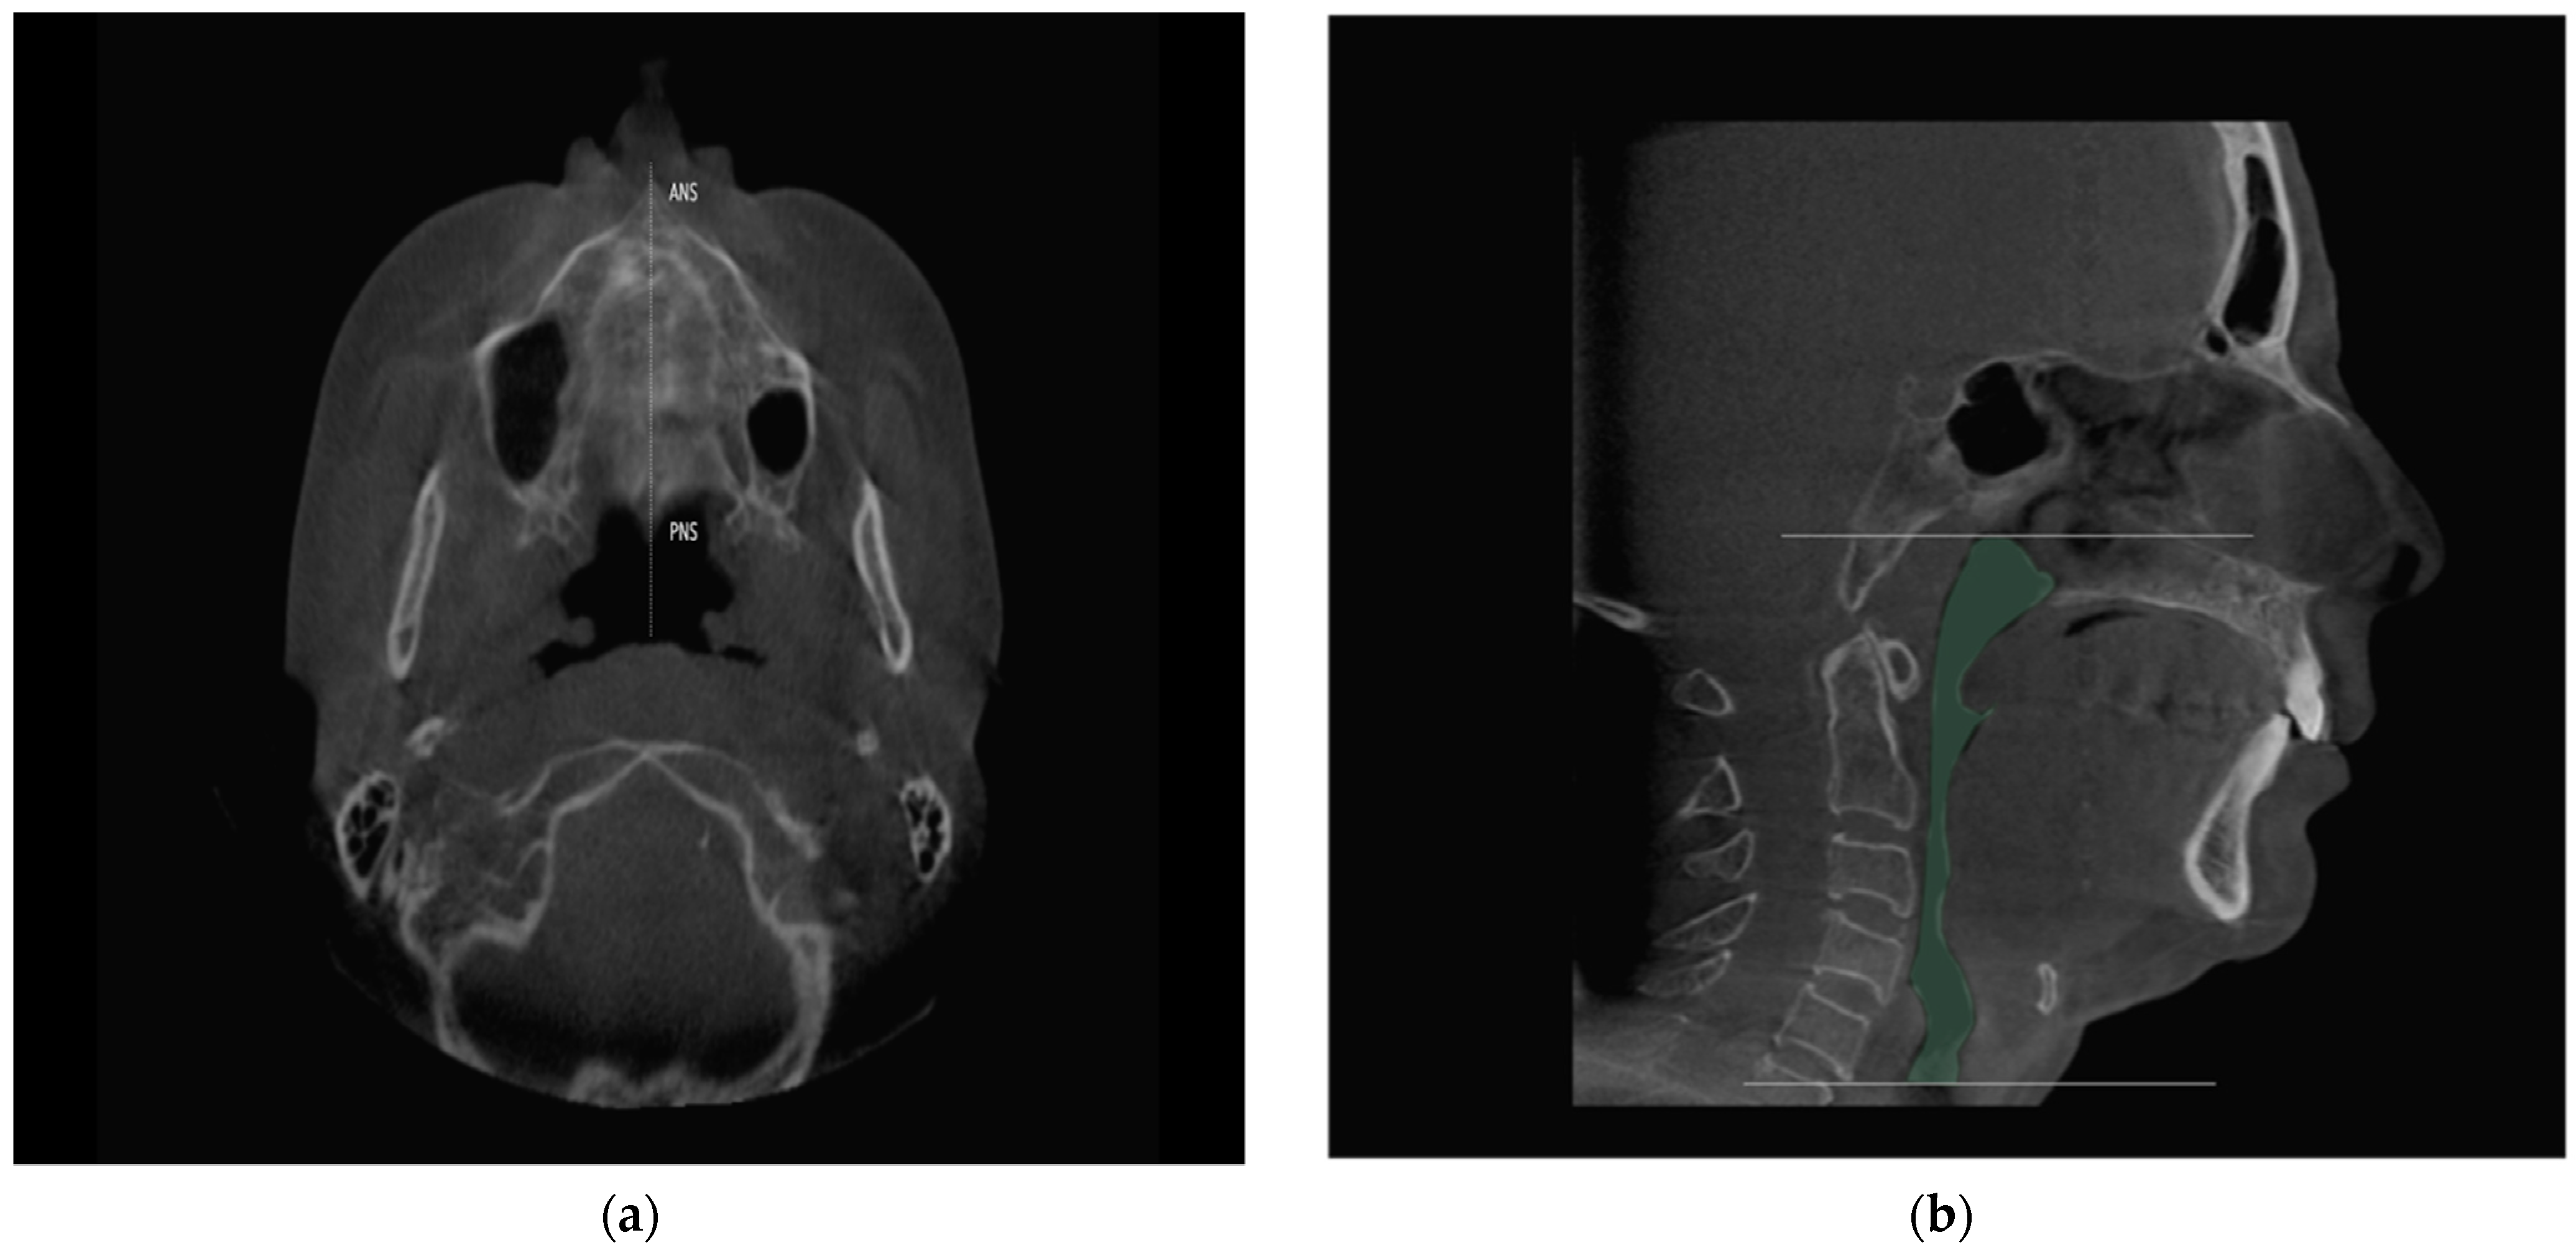

2.4. Study Variables and Data Collection